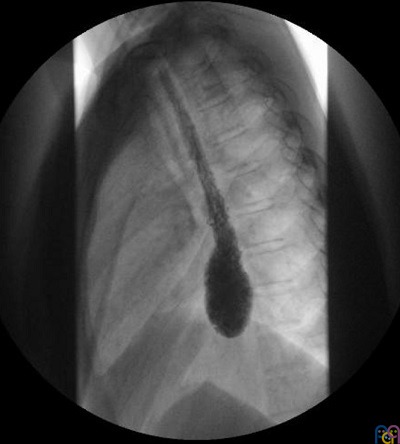

Tránsito digestivo con contraste baritado (Fig. 1): “dilatación del bolsón distal esofágico con retención de alimentos. No hay paso de contraste a través de la unión esofagogástrica. Conclusión: los hallazgos radiológicos son compatibles con el diagnóstico de acalasia”.

Esofagograma con contraste: podemos ver un esófago proximal dilatado sin contracciones peristálticas y con un estrechamiento en la unión esofagogástrica con mínimo o nulo paso de contraste al estómago a modo de “pico de pájaro”2.